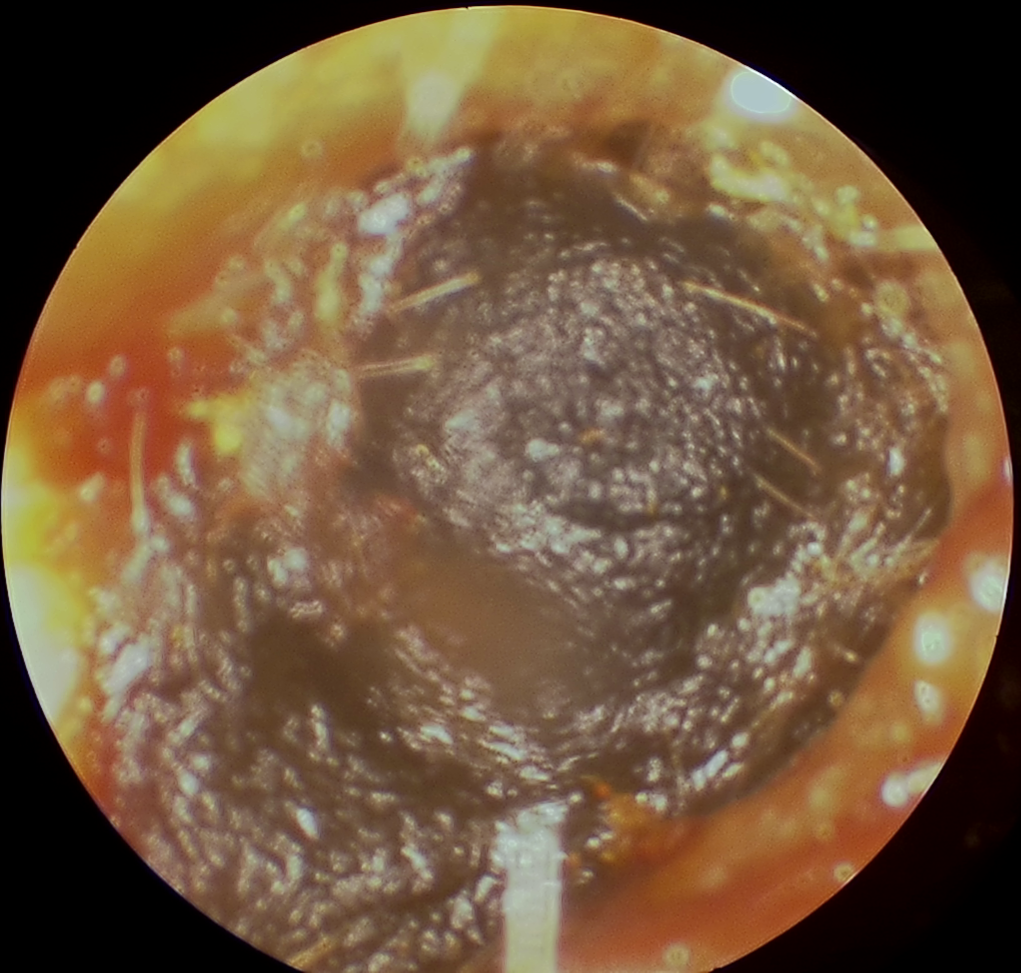

Signs of ear canal and eardrum problems

Look at these pictures of the inside of the ear. Do they look healthy?

No, the ear canal is blocked with ear wax.